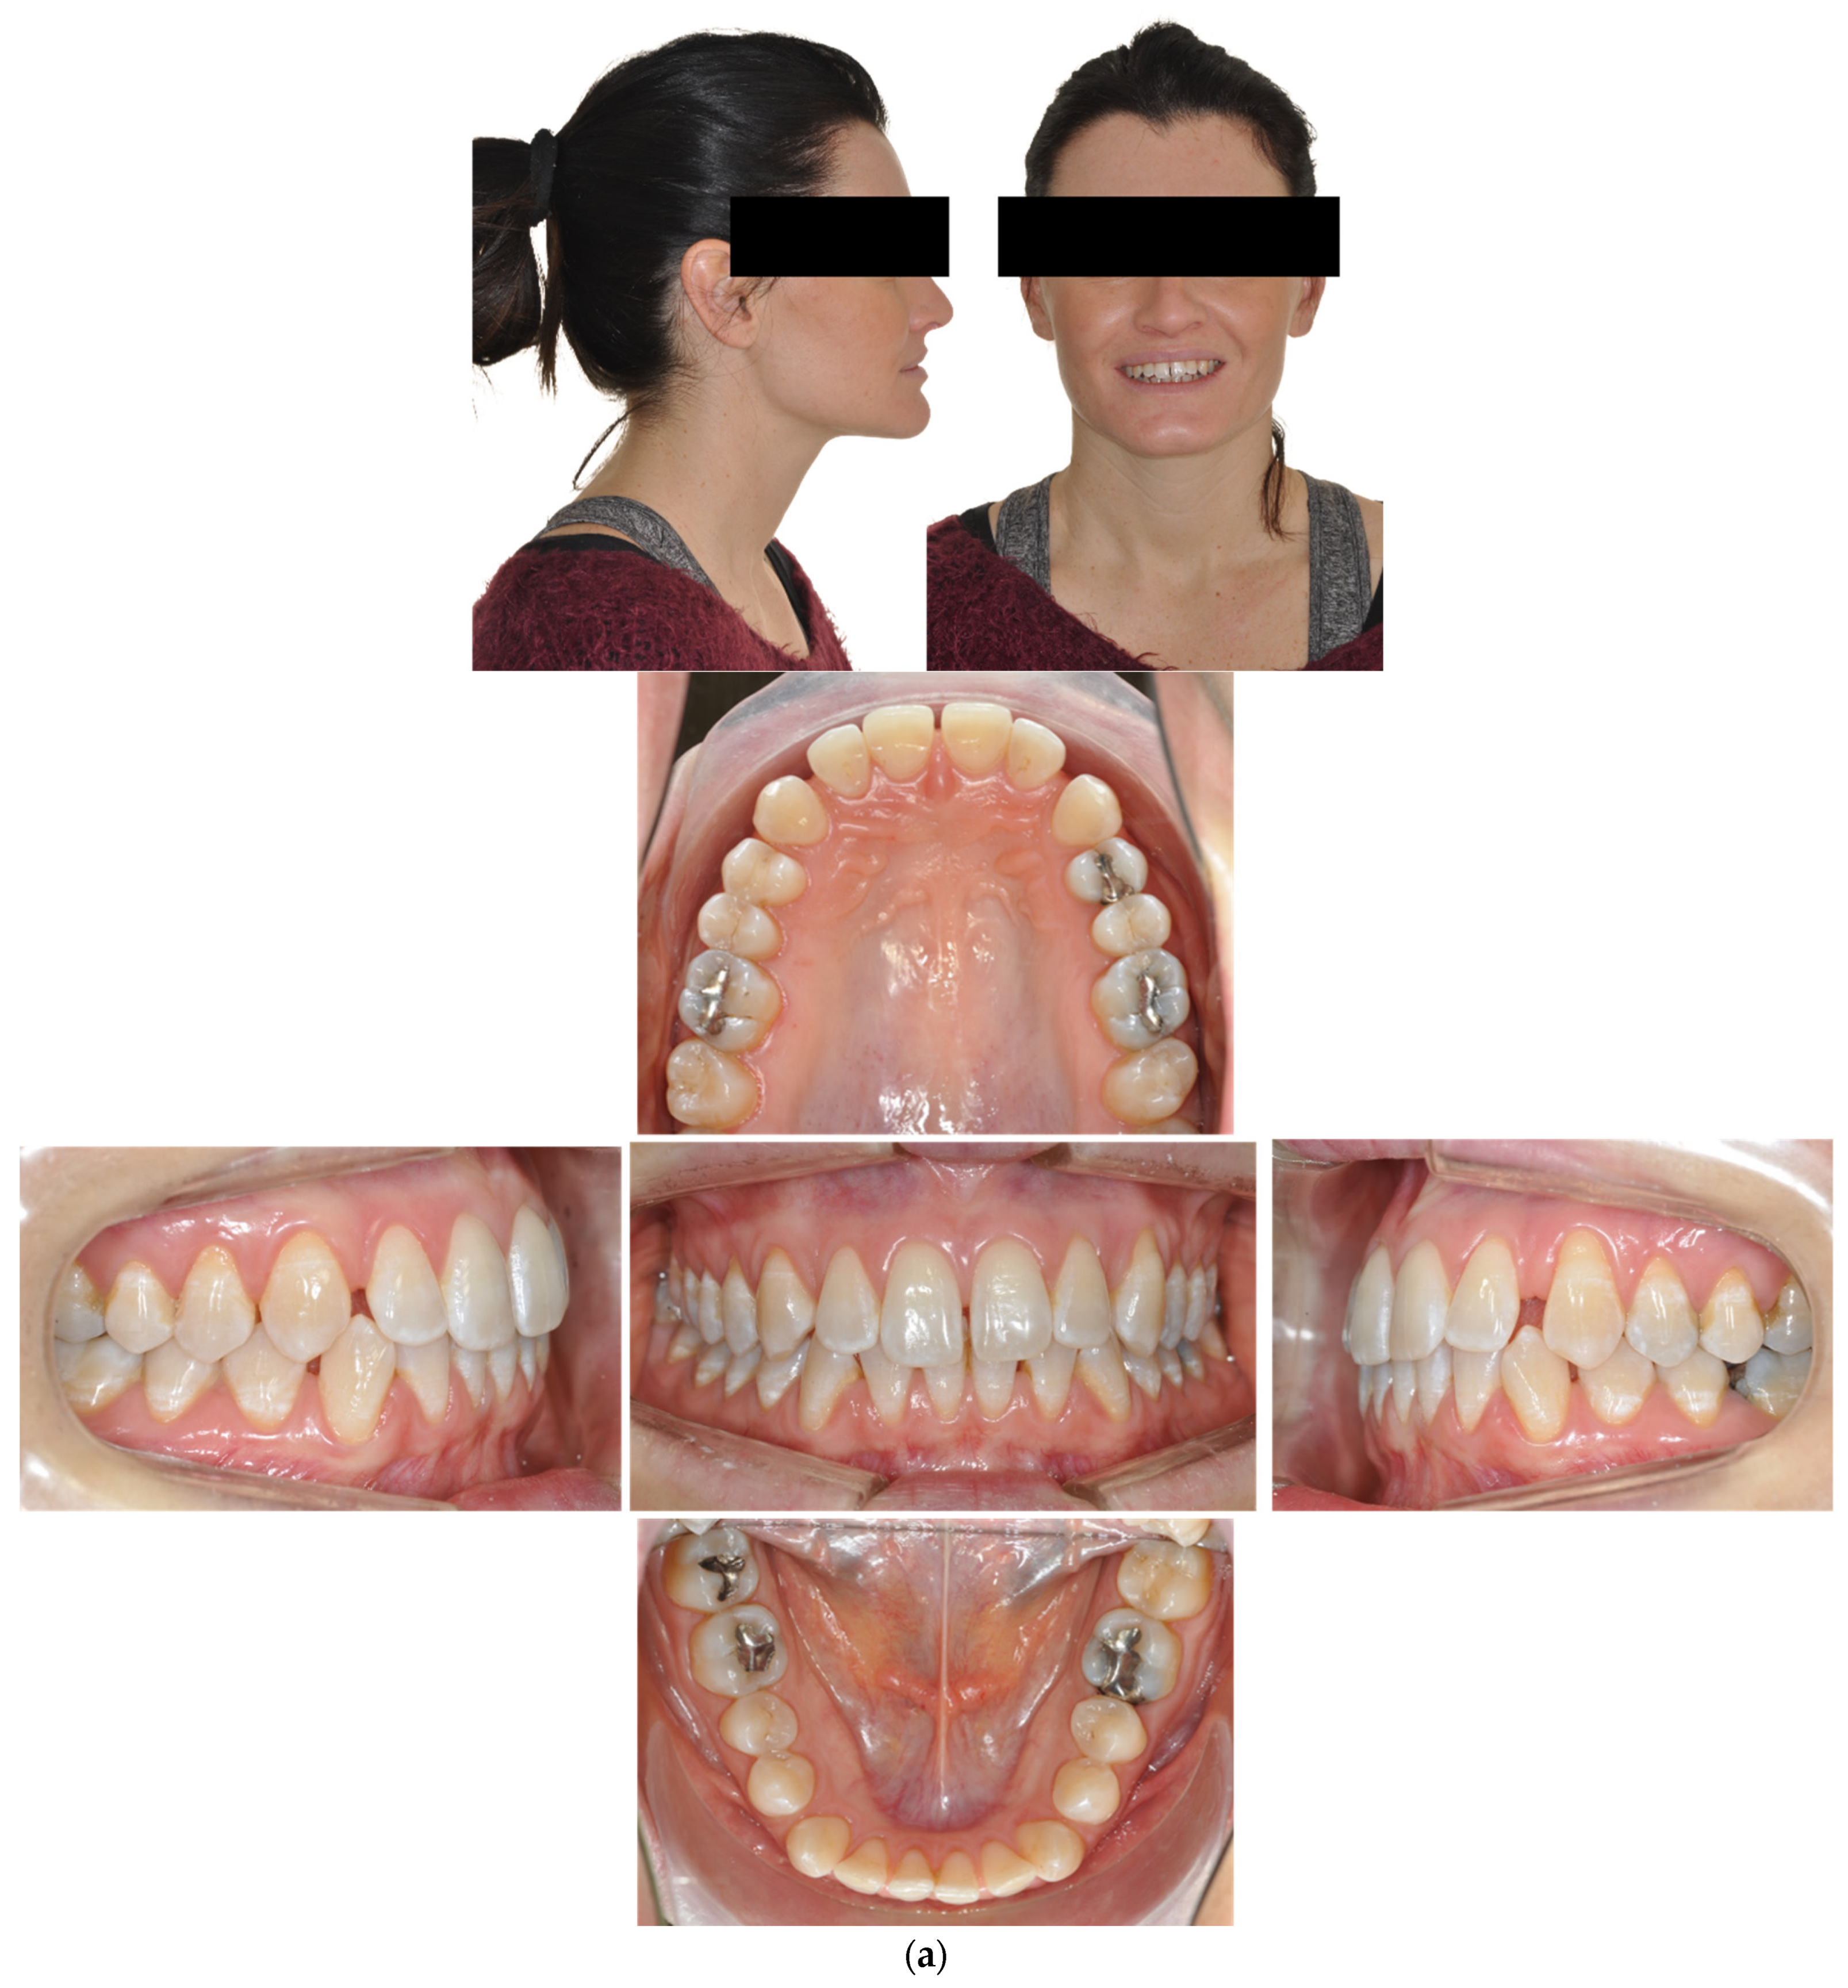

4.3. Case 3: Class II Subdivision with a Deep Bite

The patient was a 50-year-old male seeking orthodontic treatment for aesthetic reasons. His teeth were crowded, and he presented a concave profile with reduced lower facial height. An intraoral exam revealed a class II division 2 occlusal relationship and a severe deep bite in a hypodivergent facial type. There was severe crowding in both arches. The upper arch was narrow and presented a cross bite on 25. The upper midline deviated 2 mm to the right (Figure 5).

Figure 5.

(a,b) The initial images of the profile and frontal smile view and intraoral images and radiographs, including panoramic radiographs and a lateral cephalogram. (c) The digital setup performed for the treatment. (d,e) The treatment in progress with a Crozat appliance along with the aligners and lingual appliances. (f–h) Post-treatment images and a comparison with the initial images. (i) A superimposition of the pre- and post-treatment cephalograms.

The treatment objectives were to resolve the dental Class II malocclusion and achieve a Class I canine and molar relationship; eliminate the crowding, creating space for alignment, without extraction; and correct the deep bite and thereby improve the facial profile. The treatment plan chosen was a hybrid approach and IPR. The upper arch was treated initially by a Crozat appliance to achieve transversal expansion and by aligners with bite ramps to disocclude posteriorly and enhance the expansive effect of the Crozat. In the second phase, the upper arch was also bonded with Alias lingual brackets that were treated with the following archwire sequence: 0.014- and 0.016-inch CuNiti for levelling and alignment; 0.016 × 0.016-inch and 0.018 × 0.018-inch CuNiTi for rotational, tip and torque control; 0.017 × 0.017-inch SS for archform stabilisation; and 0.0175 × 0.0175-inch TMA for space closure and intrusion by loop mechanics and detailing.

In the lower arch, a Crozat appliance was used initially, followed by an Alias PSL lingual fixed appliance with the following sequence of archwires: 0.013- or 0.014- and 0.016-inch CuNiti for levelling and alignment; 0.016 × 0.016-inch and 0.018 × 0.018-inch CuNiTi for rotational, tip and torque control; 0.017 × 0.017-inch SS (stainless steel) for arch form stabilization and space closure; and 0.0175 × 0.0175-inch TMA for detailing.

After 18 months of active treatment, removable retainers were prescribed for both the upper and lower arches.

Although the correction of transverse discrepancies with good torque control is challenging with both lingual and aligner techniques [24,34,38], Case 3 (Figure 5) had a similarly successful outcome. In that case, the treatment required significant transverse expansion, along with the elimination of the deep bite and resolution of the crowding in both arches. A Crozat appliance and a partial aligner with a bite ramp/plane was used for the initial four months. Temporarily opening the posterior bite enhanced the expansive effect of the Crozat and facilitated levelling of the lower curve of Spee via the direct use of lingual appliances on the mandibular arch. The intermolar width in the upper arch was increased from 53.6 mm to 57 mm and in the lower arch from 46 mm to 48.7 mm.

Once the expansion and deep bite correction had been accomplished, lingual appliances were bonded to align the upper arch, control the upper anterior inclination and torque (perfecting the crossbite), perform intrusion and control the lower incisor inclination.